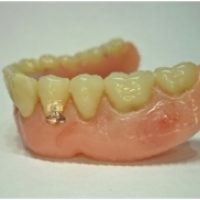

Denne løsning fungerer ved, at der indsættes implantater i kæben, der fungerer som en tryklås. På protesens bund sidder der en trykknap, som ´knappes´ fast på implantatet. Det sikrer, at protesen sidder helt fast i munden, selvom du ikke har egne tænder at sætte den fast på. Drejer det sig om en protese i overmunden, er der desuden den fordel, at din udtale bevares samt følelsen af at smagsoplevelsen bliver bedre , da protesen så kan blive ganefri.

Hvis det vurderes, at det er muligt i dit tilfælde, er det også muligt at lave en tryklåsbro i stedet for en fastskruet bro. Fordelene ved denne løsning er, at den først og fremmest ikke fylder mere i munden, end dine egne tænder gjorde. Samtidig har du mulighed for at holde en bedre mundhygiejne, da tryklåsprotesen kan tages ud af munden og rengøres.